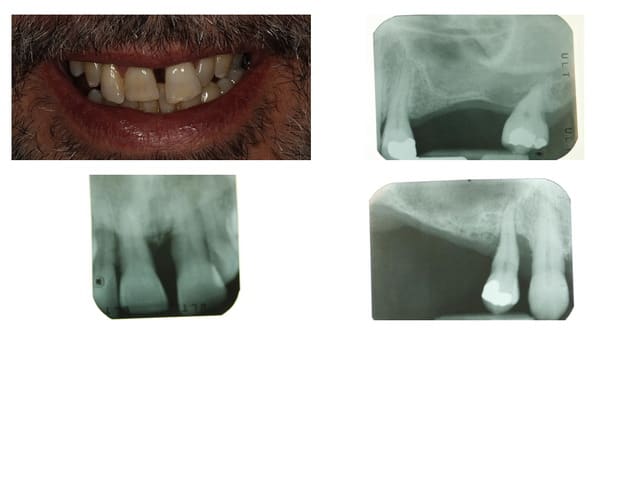

Tout à fait jeamba. Comme tu le dit très justement il n'est pas facile de pouvoir recouvrir la membrane recouvrant ton comblement à moins de :

1- faire un lambeau tracté coronairement (ce qui bride le vestibule et est préjudiciable au niveau antérieur)

2- ou bien faire un conjonctif enfoui (ou pédiculé palatin pour le maxillaire).

Une autre alternative est comme tu le dis d'extraire, d'attendre une cicatrisation des tissus mous (2 à 4 semaines) avant de passer au comblement.

J'ai également trouvé une autre alternative dont je n'ai vu personne d'autre utiliser. Comme vous êtes sympas je vous fait part de ce petit truc utile: prenons l'exemple présenté sur le photos ci jointe où une 22 fracturée doit être extraite. Le principe que j'ai mis au point est de meuler la 22 de facon à enfouir la racine à un niveau sous gingival, quaisiment juxta osseux et d'attendre quelques semaines avant de passer à l'extraction. Cela à pour conséquence un recouvrement radiculaire par les tissus gingivaux. Une fois la racine enfouie, je n'ai plus qu'à ouvrir, extraire au periotome, faire mon comblement si besoin, placer ma membrane et suturer mon lambeau sans avoir à le tracter, ou presque.